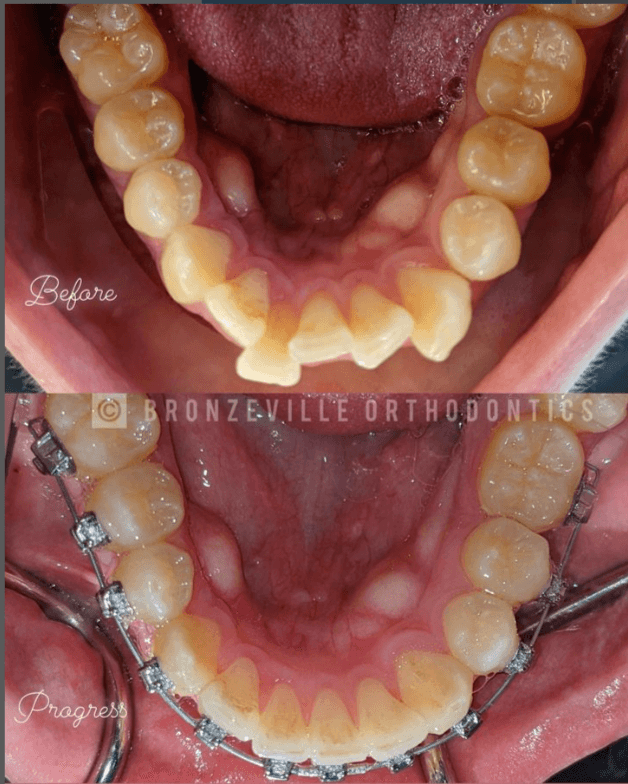

I believe the success of my brand has been authenticity and being able to connect with people in the community. I do my best to show up authentically as myself first and create that type of culture within the orthodontic office as well. We are not your typical orthodontic office. I am not what your typical orthodontist looks like. From our decor, to the music, to the artwork, to the sneaker fashion. We are a “vibe” as our patients and patrons like to call it. And not to mention last, but we deliver on the results. I have strong desire to help elevate the oral health and overall health of my community via dentistry and orthodontics. But I believe in order to do that, especially in an underserved community with high dental anxiety, you have to gain trust, you have to be relatable. People have to know and feel your intentions. I believe when people come into our office they can instantly feel the vibes and the intentions. Also knowing that I’m from the community and showing them what it means to build a successful black owned business from the ground up while living in the community. It feels like they’re rooting for me

Bronzeville Orthodontics is a community accessible, high-quality, specialty orthodontic practice. Our mission is to provide access to world-class digital and virtual orthodontic care for children and adults in Bronzeville and surrounding communities of Chicago. We specialize in the diagnosis, prevention, and correction of teeth and jaw irregularities that can lead to dental disease. Bronzeville Orthodontics offers services in the form of traditional braces, clear aligner therapy, ceramic braces, lingual braces or hidden braces, retainers, teeth whitening, and other smile-enhancing treatments.